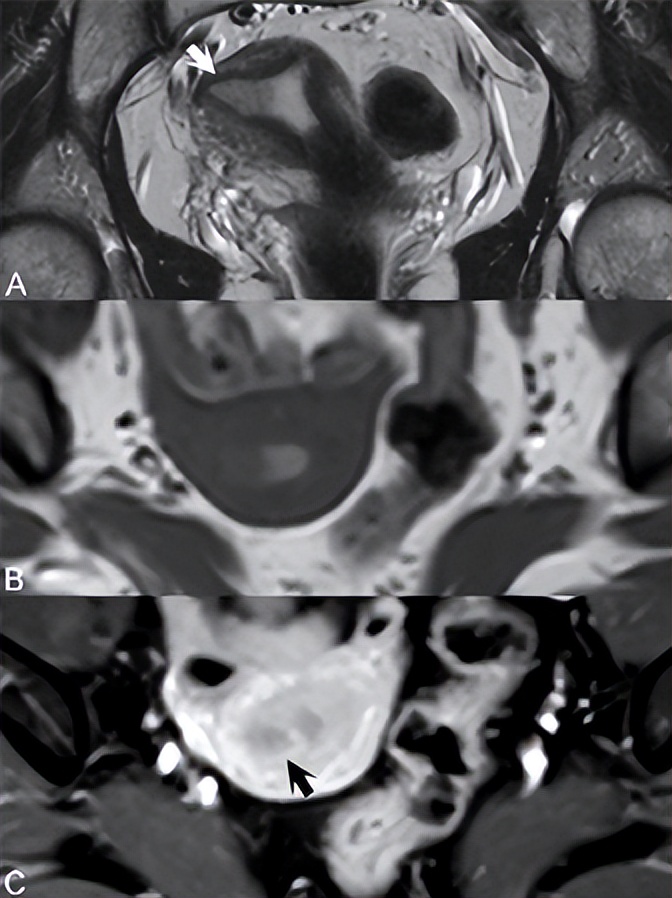

子宫内膜癌易受子宫内膜增生和息肉发展的影响,磁共振在鉴别后者的良性和恶性方面用处不大。良性和恶性息肉的信号不同,后者只能通过子宫肌层浸润来识别。粘膜下肌瘤可能看起来与恶性息肉相似,但起源于子宫肌层,除非变性,否则表现出均匀的低信号。绝经前妇女的子宫内膜厚度因月经周期阶段和激素水平而有很大差异。在无阴道出血的绝经后妇女(PMP)中,子宫肌层厚度为11 mm可作为转诊宫腔镜检查的临界点,而所有有阴道出血的PMP妇女都需要进行子宫内膜评估。T2WI上囊性扩张的高信号腺结构通常存在于增生性子宫内膜中,且通常不会增强。在MR上,子宫内膜增生的结果与子宫内膜癌的结果无法区分,只有子宫肌层浸润可以证明后者——女性生殖道最常见的浸润性癌。治疗以分级为指导,但由于T2WI对结合带解剖结构的描述准确,因此采用MR进行早期分期。如图75.1所示,1A期病变表现为子宫内膜增厚,无结合带区破坏。(A)冠状位T2WI上,低信号病变(白色箭头)累及子宫内膜右侧。(B)轴位T1WI上存在低信号病变,但未描绘结合带解剖结构。(A) T2WI中在1B病变中破坏的结合带明显完整,因此确定为1A期。如果结合带和子宫肌层之间的区别很差,如在子宫腺肌病或绝经后患者中,则CE T1WI通过描绘与子宫内膜癌相对应的早期子宫肌层增强缺失区域来帮助诊断。图75.1C中的轴位CE T1WI显示完整的高信号子宫肌层,低信号癌(黑色箭头)局限于子宫内膜。在延迟图像上,子宫肌层出现高信号,类似于纤维瘤。区分1B期和1C期疾病至关重要,后者与子宫外和淋巴转移的高度相关。

▲ 图75.1

MR通过结合带的完全破坏可靠地识别1C期病变,局限于但累及一半以上的子宫肌层。最近,扩散加权成像(DWI)被认为在子宫肌层浸润的术前评估中具有较高的诊断价值。